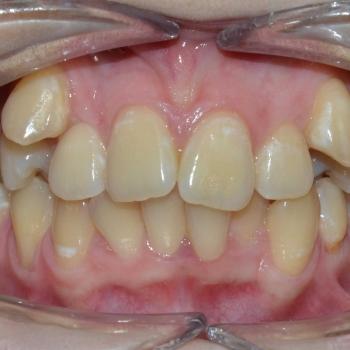

Luca saját elhatározásból, az alsó és felső fogív torlódása, de főleg a két felső szemfog ectopiás helyzete miatt keresett fel. Már elsőre pillantásra látható volt és Luca is sejtette, hogy foghúzások nélkül az Ő esete nem oldható meg,de szerencsére ez nem tántorította el a céljától.

Közös döntés eredményeként fém önligírozó fogszabályozót választottunk, illetve a felső kisőrlők, illetve egy darab alsó metszőfog eltávolítására került sor. Az alsó metszőfog eltávolítása elsőre szokatlannak tűnhet, de a fogszabályozásban ez bevett gyakorlat hiszen esztétikai problémát nem okoz és a húzás által biztosított plusz hely rögtön a megfelelő helyen áll a rendelkezésünkre.